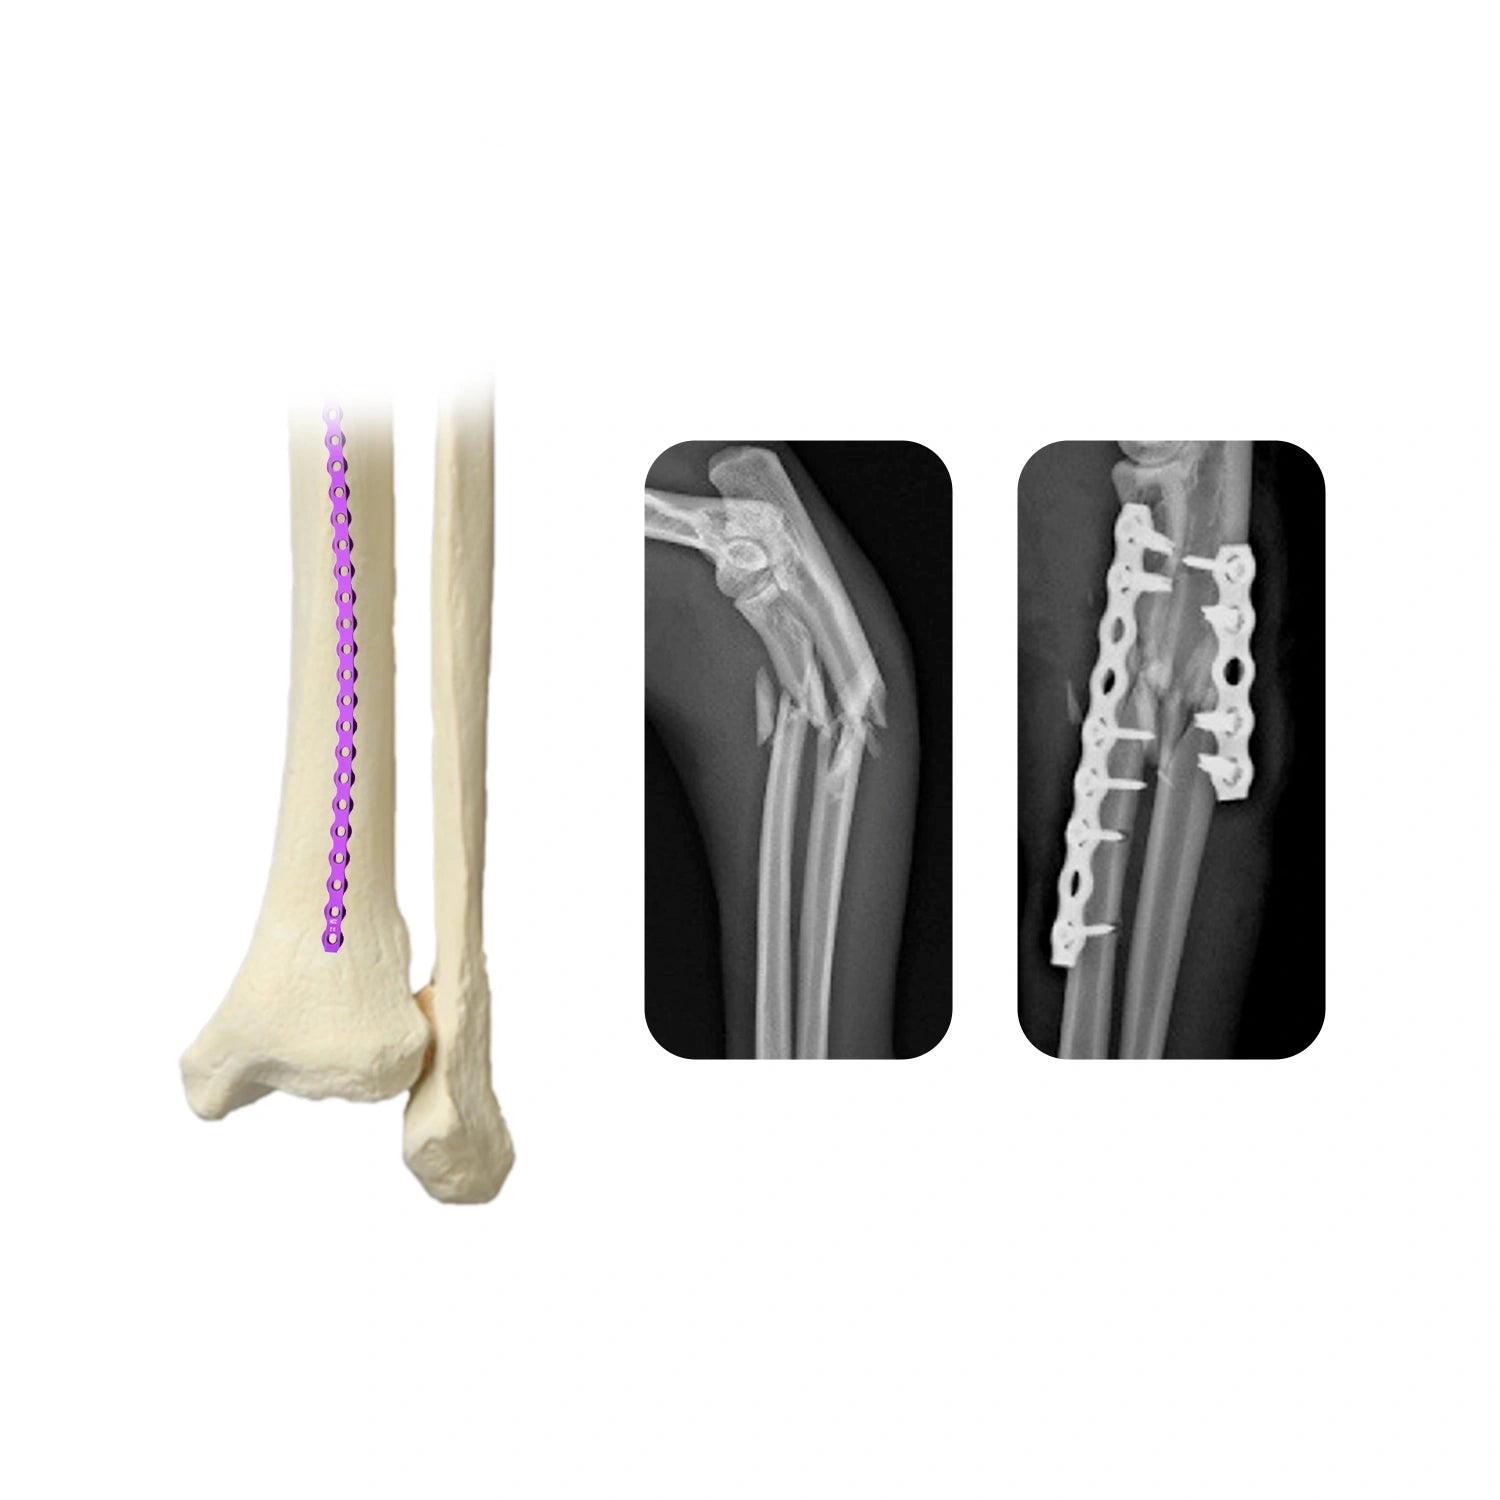

2.0mm Veterinary AO Orthopedic Implants Titanium Reconstruction Locking Plate

Veterinary 2.7mm AO Reconstruction Locking Plate Premium Ortho Implant

Veterinary 2.4mm AO Reconstruction Locking Plate Reliable Fixation for Small Animal Orthopedics